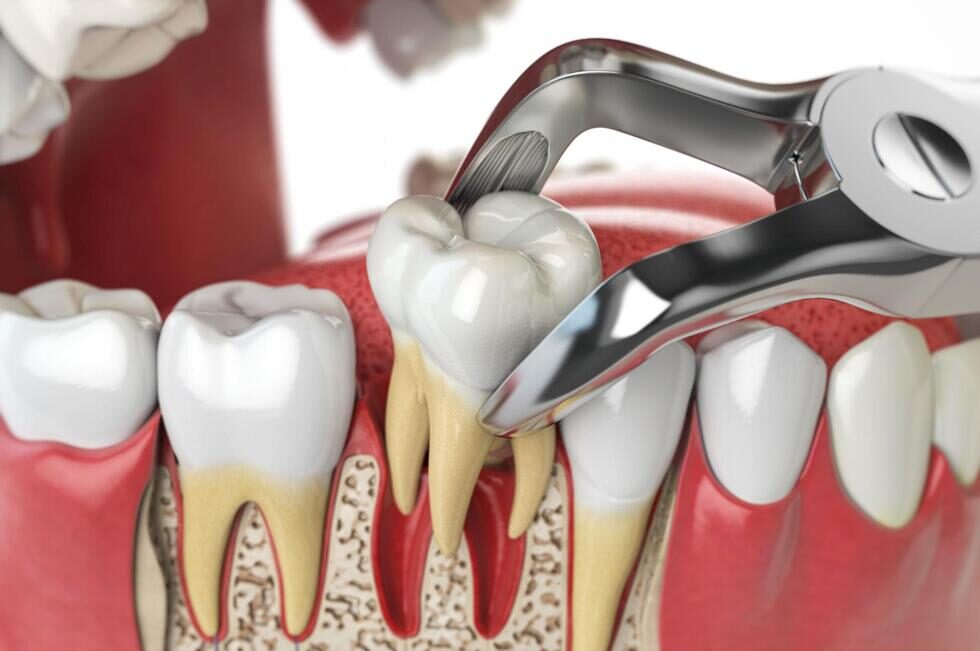

抜歯

親知らずを抜く方法は、生え方によって異なります。まっすぐ生えている場合は、専用の器具を使って、歯を脱臼させてから抜きます。横向きや斜めに生えている場合は、そのままでは抜けないため、歯を小さく切り分けてから順番に取り出していくことが多いです。歯を切り分ける際は、専用のドリルを使います。水で冷却しながら行うため、熱による痛みもありません。